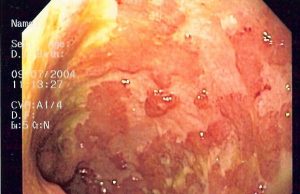

Colite ulcerosa: risultati promettenti nella cura con l’anticorpo monoclonale tulisokibart

Uno studio di fase 2 su un anticorpo monoclonale noto come tulisokibart, utilizzato in pazienti con colite ulcerosa da moderata a grave, ha mostrato...